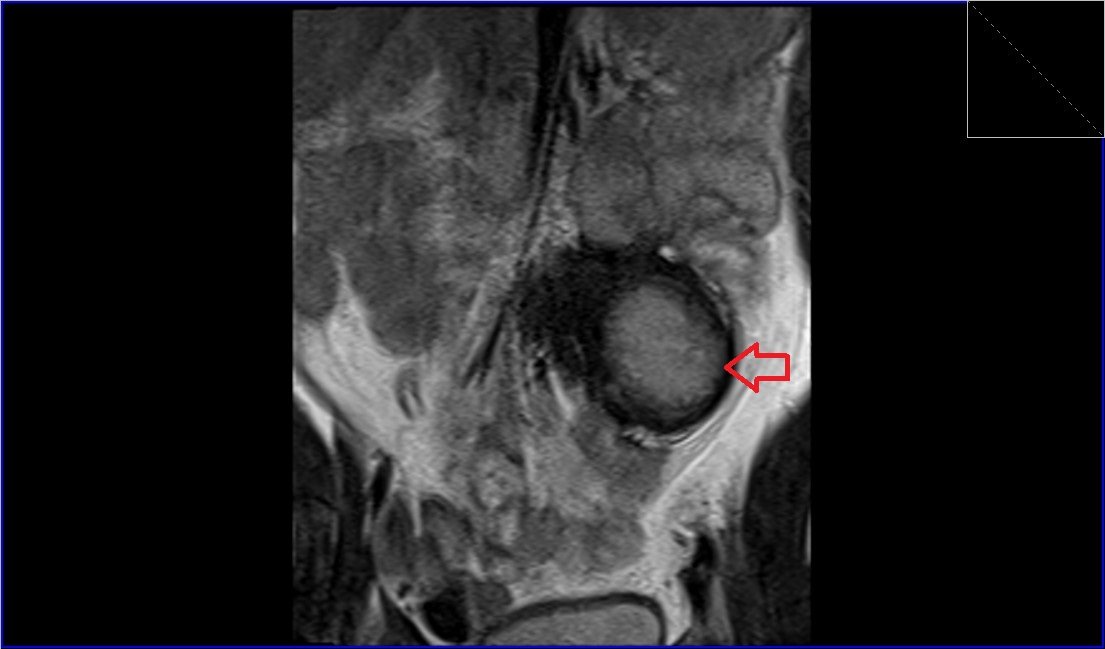

MRI abdominal pathologies FNH LIVER Haemangiomas Liver Choledocholithiasis Renal cell carcinoma Abdominal Wall AVM Gallstones Retroperitoneal desmoid Hepatocellular carcinoma (HCC)